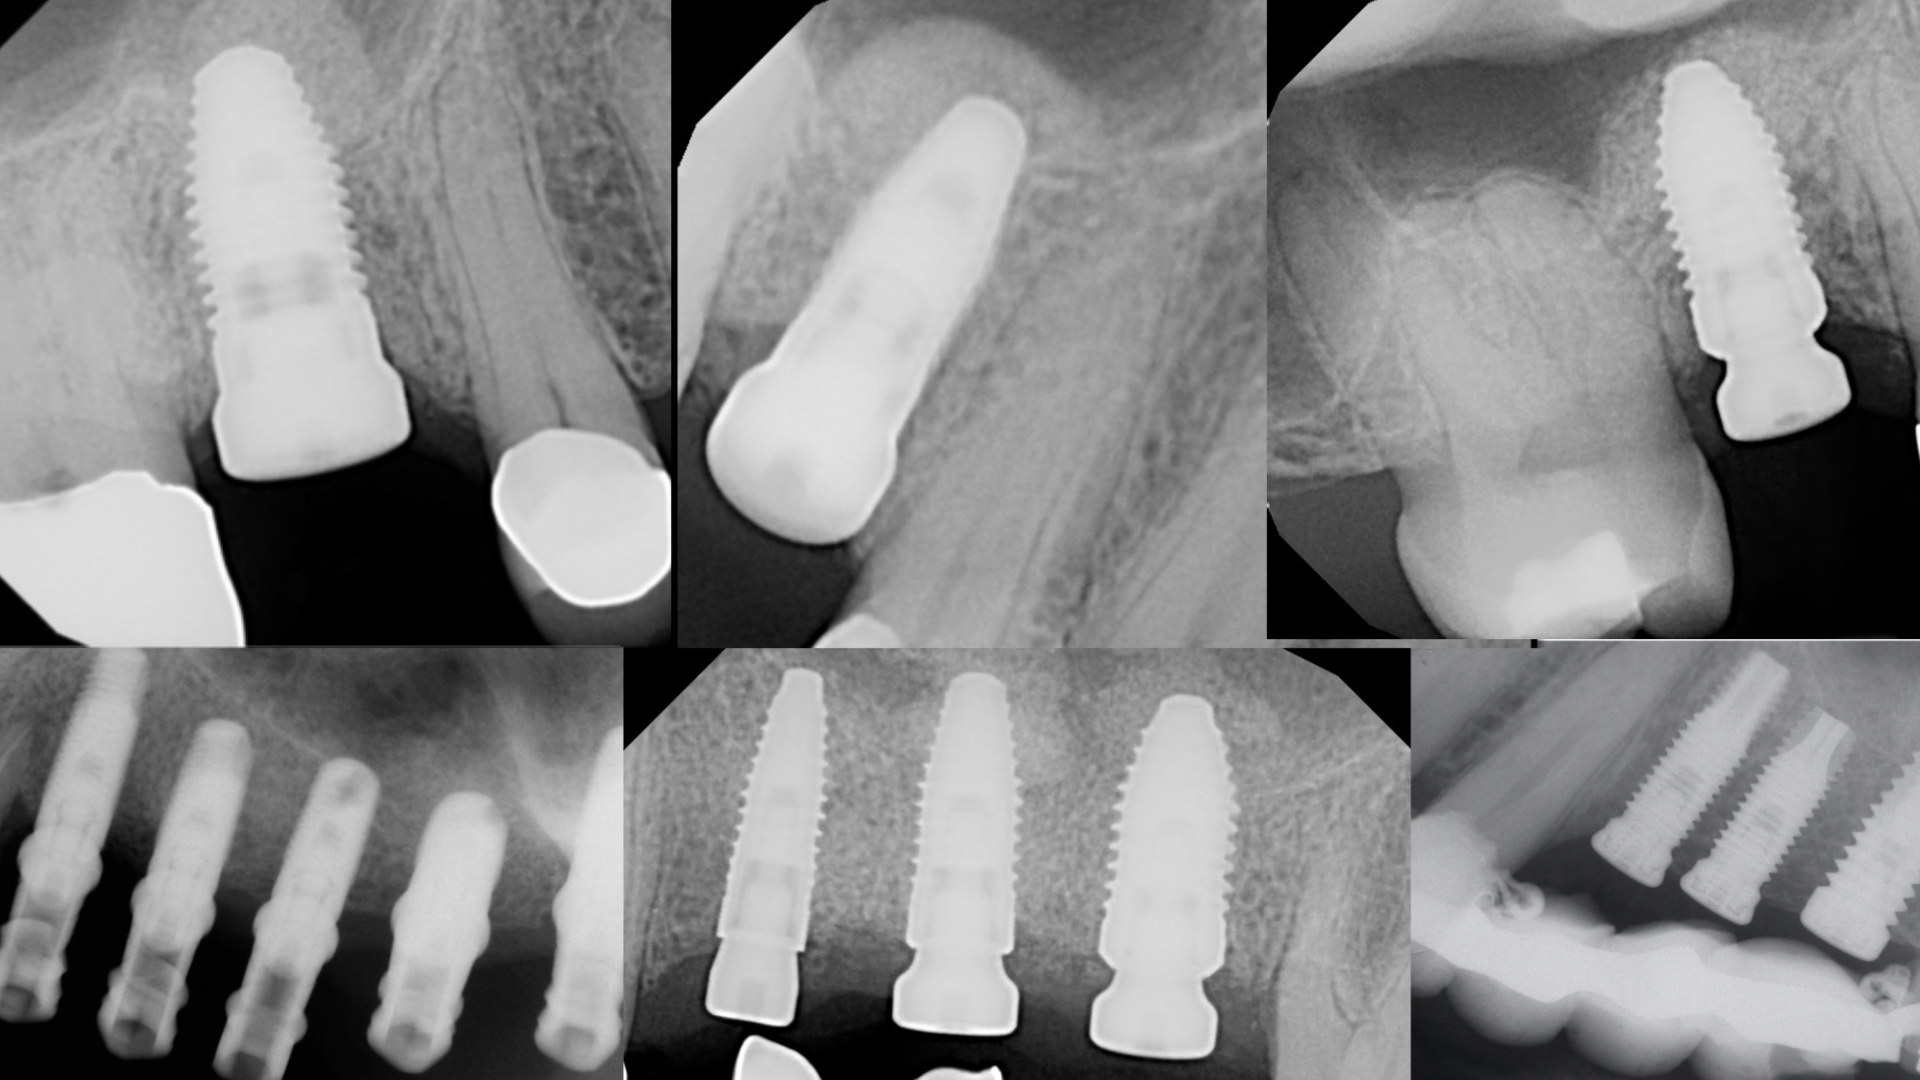

- When a crestal sinus lift is indicated

- Step-by-step direct sinus lifts

- When a lateral window sinus lift is indicated

- Step-by-step lateral window sinus lift

Because >50% of all upper molar implants need some sort of sinus lift.

Perform twice as many implants with full confidence.

Dr. Ziv Simon will present a proven system that you can start using immediately regardless of what level you are at to develop mastery in sinus lift surgeries. You will be provided with a roadmap working document that you can use the next day in your practice to give you clarity when treatment planning patients who need sinus lifts.